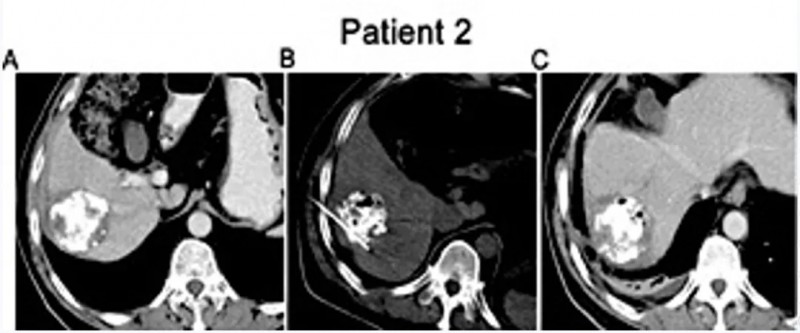

一项发表在《Cellular Physiology and Biochemistry》的研究显示,不可逆电穿孔(IRE)联合同种异体NK细胞治疗IV期肝细胞癌(HCC)具有显著优势。

该研究共纳入40例患者,分为IRE单独治疗组和IRE联合NK细胞组。结果证实,联合治疗组在多个指标上均优于对照组:

- AFP水平显著下降:治疗3个月后,联合组中有11例患者AFP恢复正常;

- 肿瘤体积缩小:联合组肿瘤直径显著小于对照组;

- 疾病控制率(DCR)高达90%,远高于对照组的75%;

- 中位总生存期(OS)延长至10.1个月,相比对照组8.9个月更具优势。

尤其令人振奋的是,有两例患者在联合治疗后达到完全缓解(CR)。一例44岁男性患者,经联合治疗后MRI显示肿瘤无强化,病灶萎缩;另一例52岁女性患者,影像显示肿瘤大面积坏死,疗效持续稳定。

数据来源:Cell Physiol Biochem,医学部汇总

这些结果说明,NK细胞联合局部消融治疗,尤其对于晚期肝癌患者,不仅能有效控制肿瘤进展,还可延长生存期,改善生活质量。